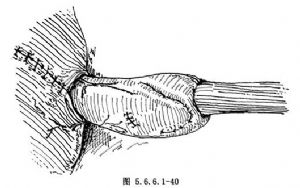

(8)将抵钉座之中心杆尾端通过上述小戳口插至吻合器主体内,使二者重新对合并旋紧尾端螺丝,调节间距,使被吻合的食管和胃两端紧密靠拢(图5.6.6.1-40)。